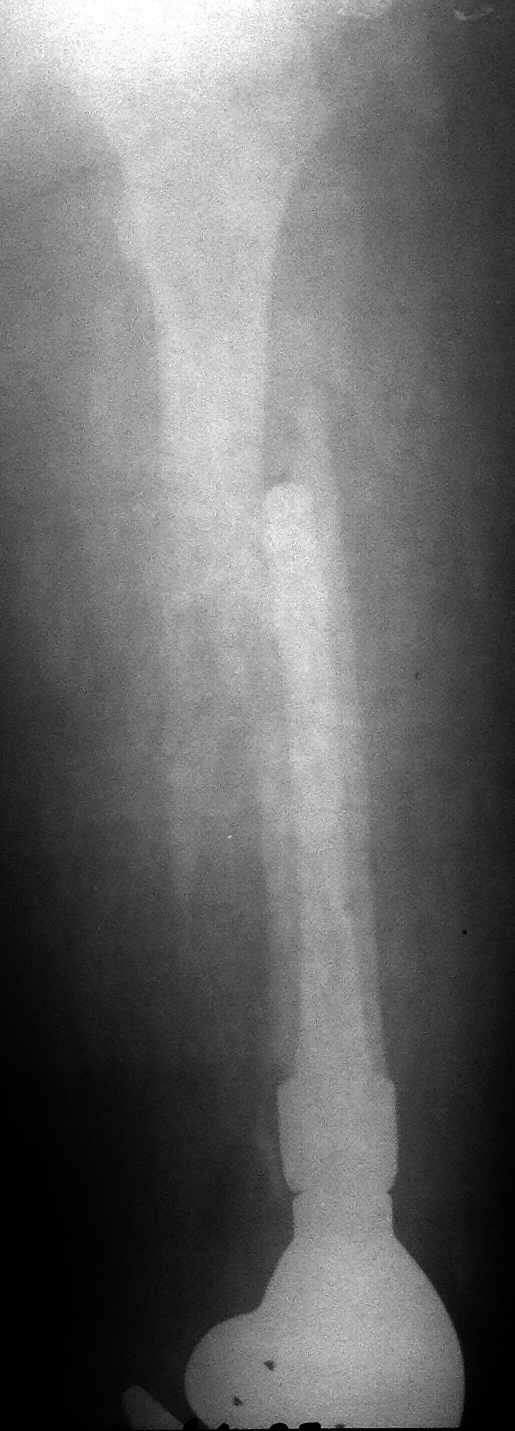

Молодая девушка, оперирована в 2012 году по поводу опухоли (какой не

знает, выписки потеряли). Получила травму при падении. Пациентка

избыточного веса. Ваша тактика?

Я прошу прощения за качество снимков (рентген сломалcя, снималось

"палатником"). Если где-то не видно - длинный спиральный перелом, ножка

полностью заполняет костно-мозговой канал, цемент дошел до малого вертела.